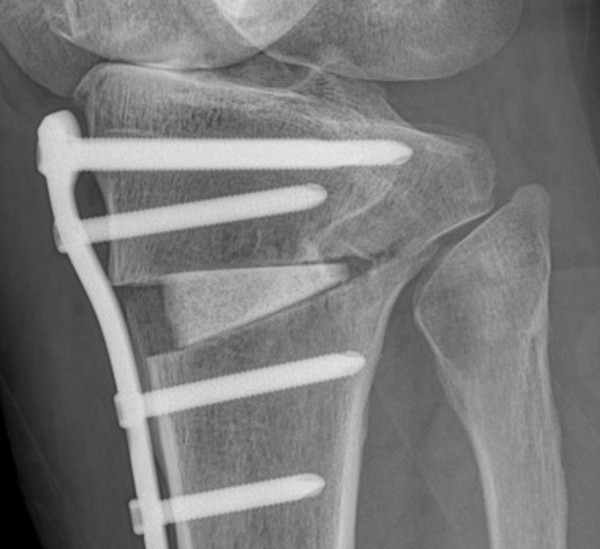

#절골수술(Osteotomy)의 이해

절골수술은 무릎 관절의 비정상적인 정렬을 교정하기 위한 수술적 방법입니다. 이 수술은 주로 관절염으로 인한 통증과 기능 장애를 겪고 있는 환자들에게 시행됩니다. 수술 과정에서는 뼈를 절단하고 재정렬하여 무릎에 가해지는 압력을 분산시킴으로써, 관절에 대한 스트레스를 줄이고 통증을 완화시킵니다. 이러한 접근법은 관절의 수명을 연장시키고, 궁극적으로는 관절 교체 수술을 피할 수 있게 해줍니다.